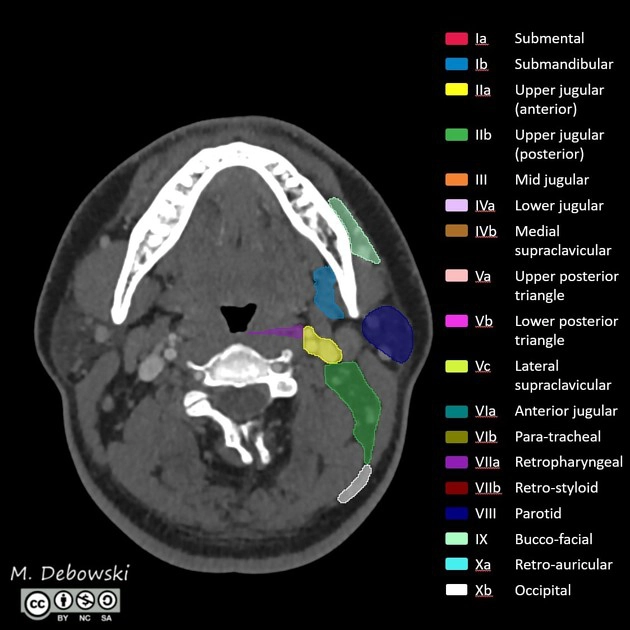

Các nhóm hạch cổ (Lymph node levels of the neck)